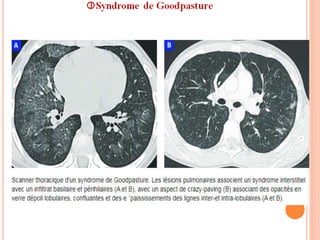

 Imagerie:

 TLX: Infiltrats bilatéraux variables, péri-hilaires.

 TDM: VD +++ et condensations à localisation Images

centrale épargnant la périph. d’HIA

 Parfois asymétriques, rarement unilatéraux.

 Pas d'EPL ni d'ADP.